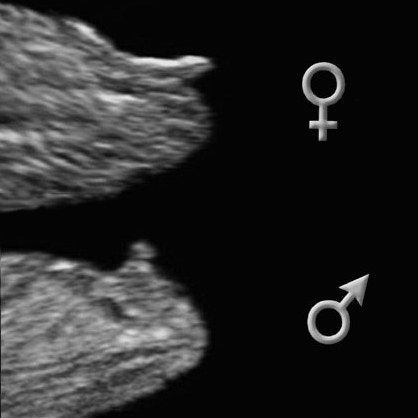

Правильная визуализация любой части плода зависит от многих факторов, таких как положение плода, количество амниотической жидкости и толщина брюшной стены. Такие удачные картинки как на фото слева получаются крайне редко. У кого больше?

Определение происходит за счет анализа угла между половым бугорком и спинкой малыша.

12-недельный эмбрион – (размер эмбриона 75 мм) – 14 акушерских недель беременности

Мальчик

У мальчиков половой бугорок образует угол примерно 30 градусов или больше со спинкой.

Девочка

У девочек половой бугорок образует угол меньше 30 градусов.